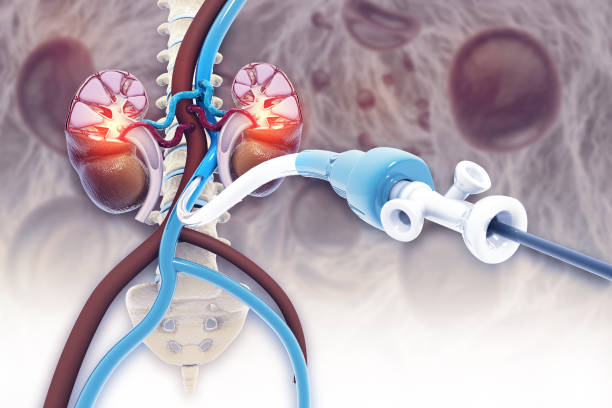

요로결석은 소변으로 배출되지 못한 미네랄 염물이 결정으로 변화하여 요로 기관을 막거나 염증을 유발하는 위험한 질환입니다.

요로결석은 요로(요관, 방광, 요도)에 생기는 결석으로, 소변으로 배출되지 못한 미네랄 염물이 결정으로 변화해 쌓이는 질환입니다. 이 결정들이 소변 기관을 막거나 염증을 유발하여 신체에 피해를 줄 수 있습니다.